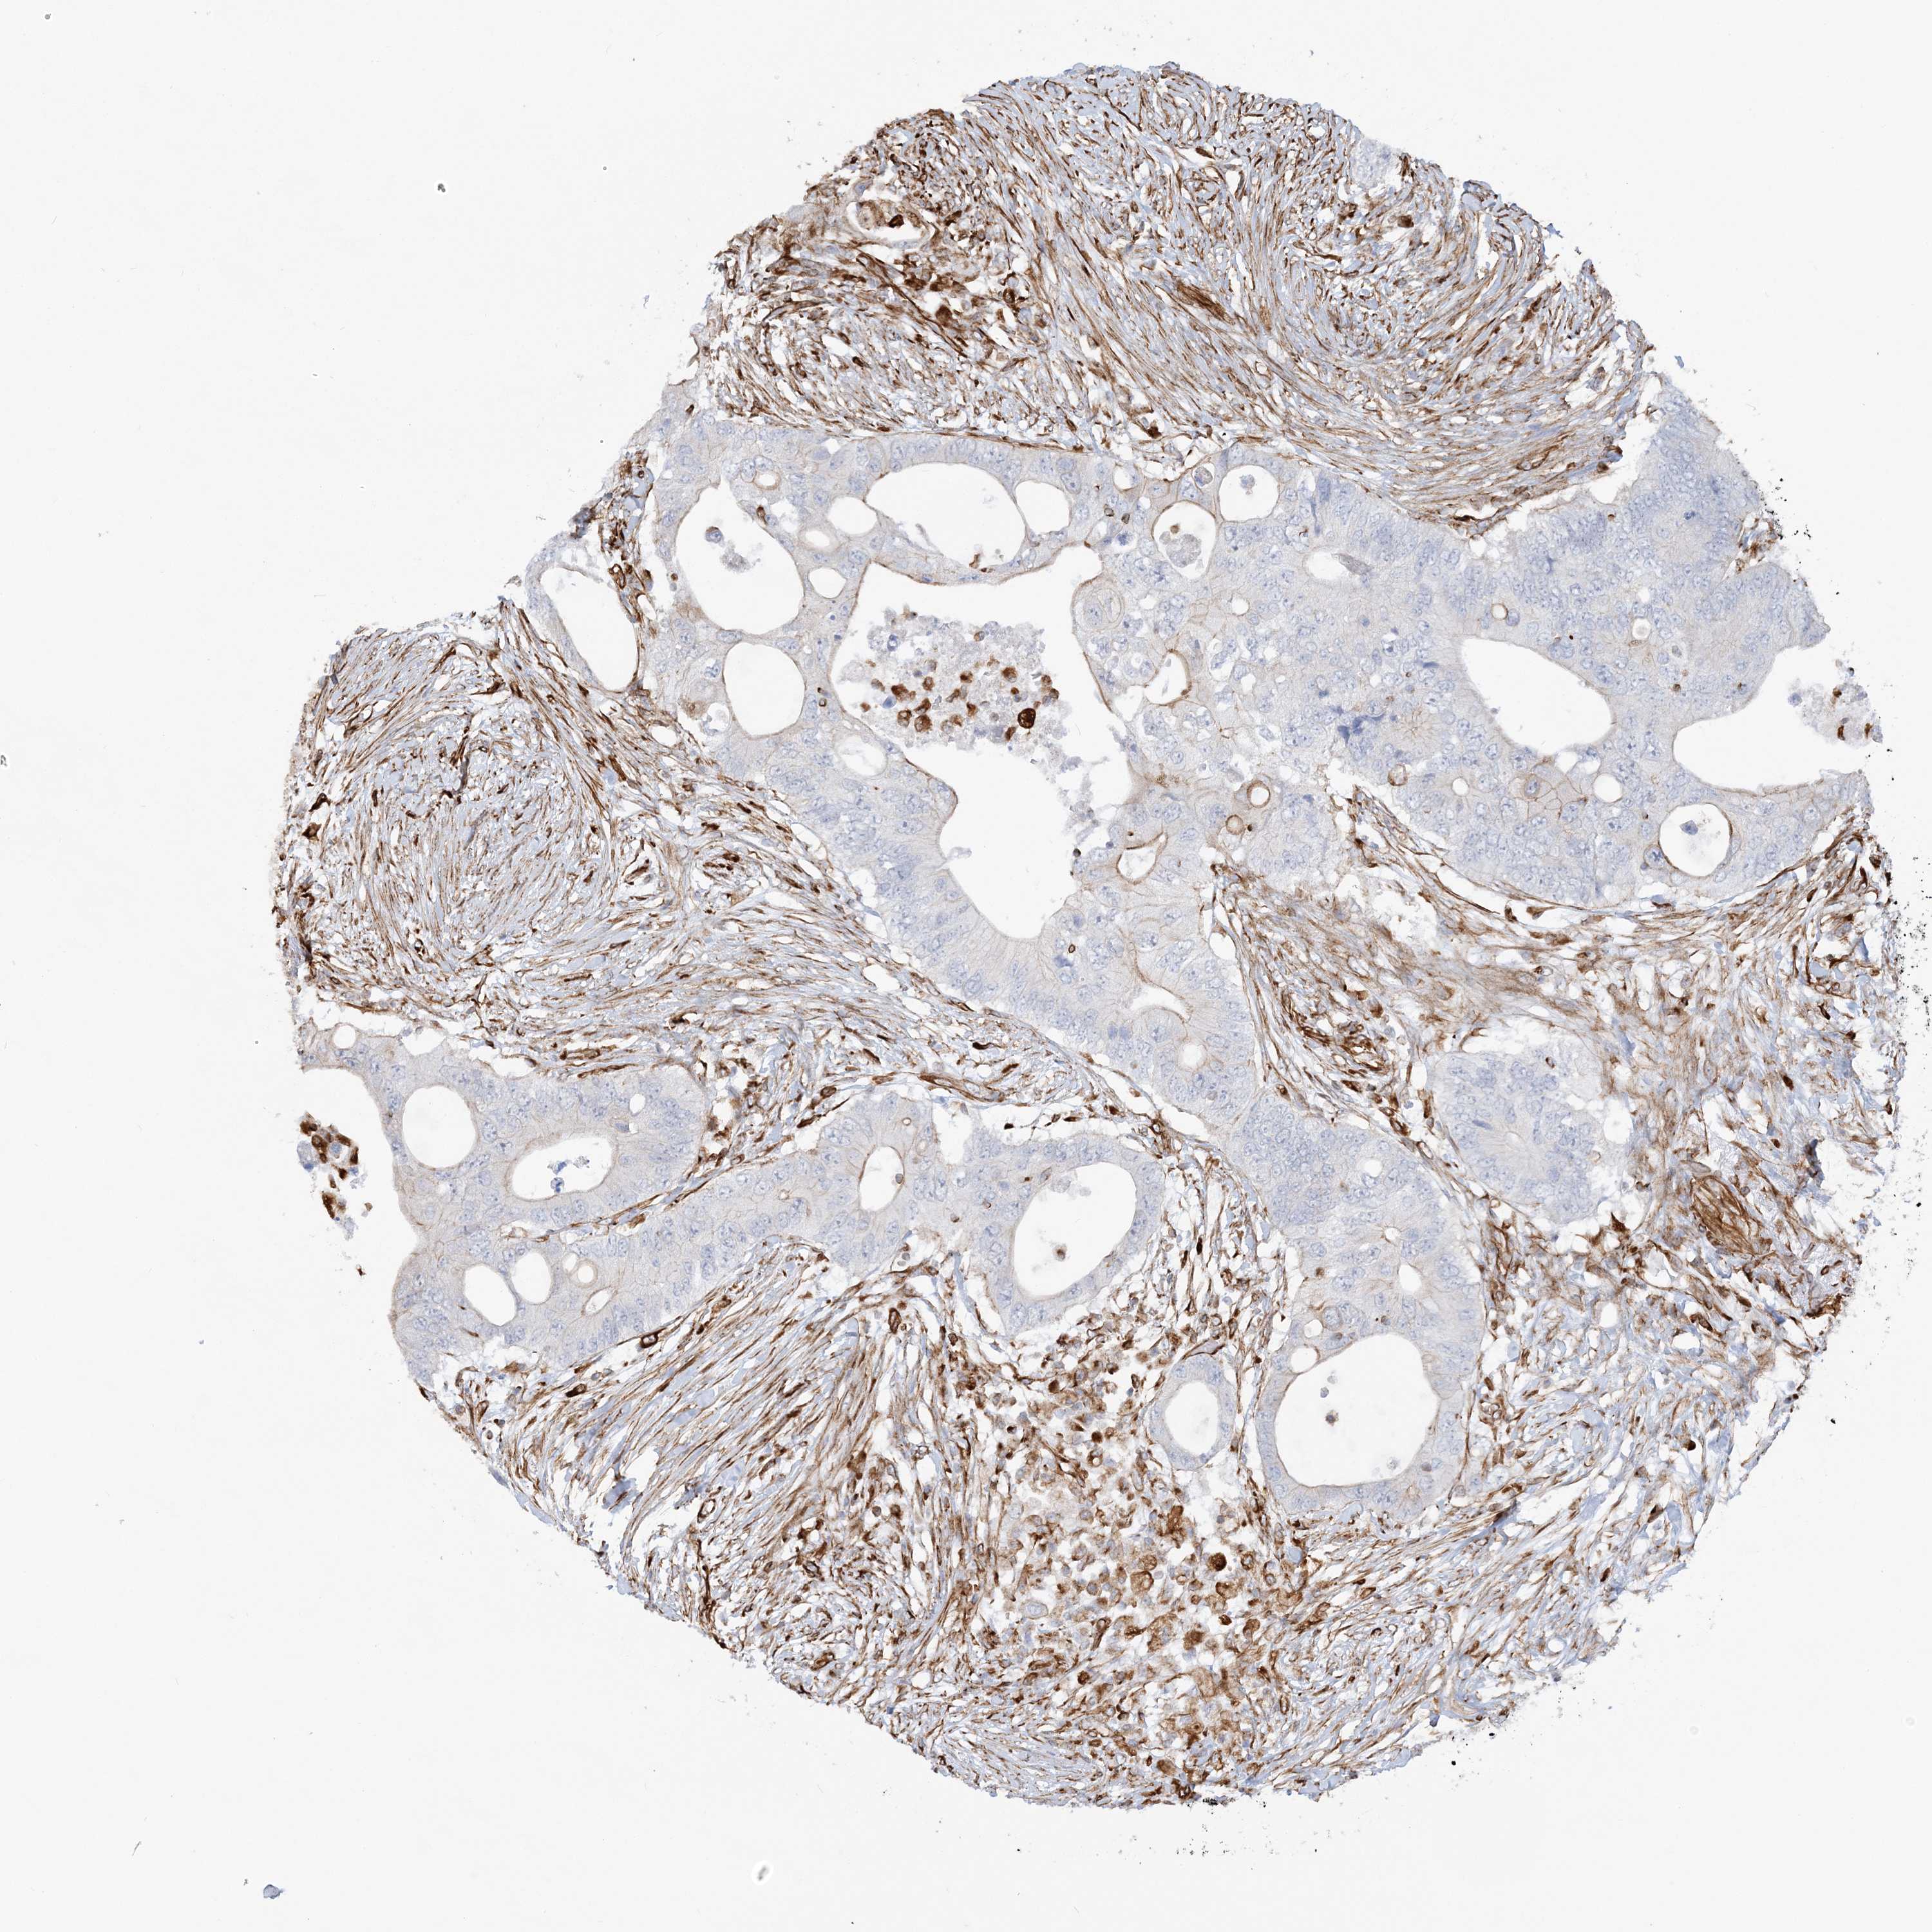

CANCER COLORECTAL CANCER Show tissue menu

Colorectal cancer

Human cancer

Colon adenocarcinoma